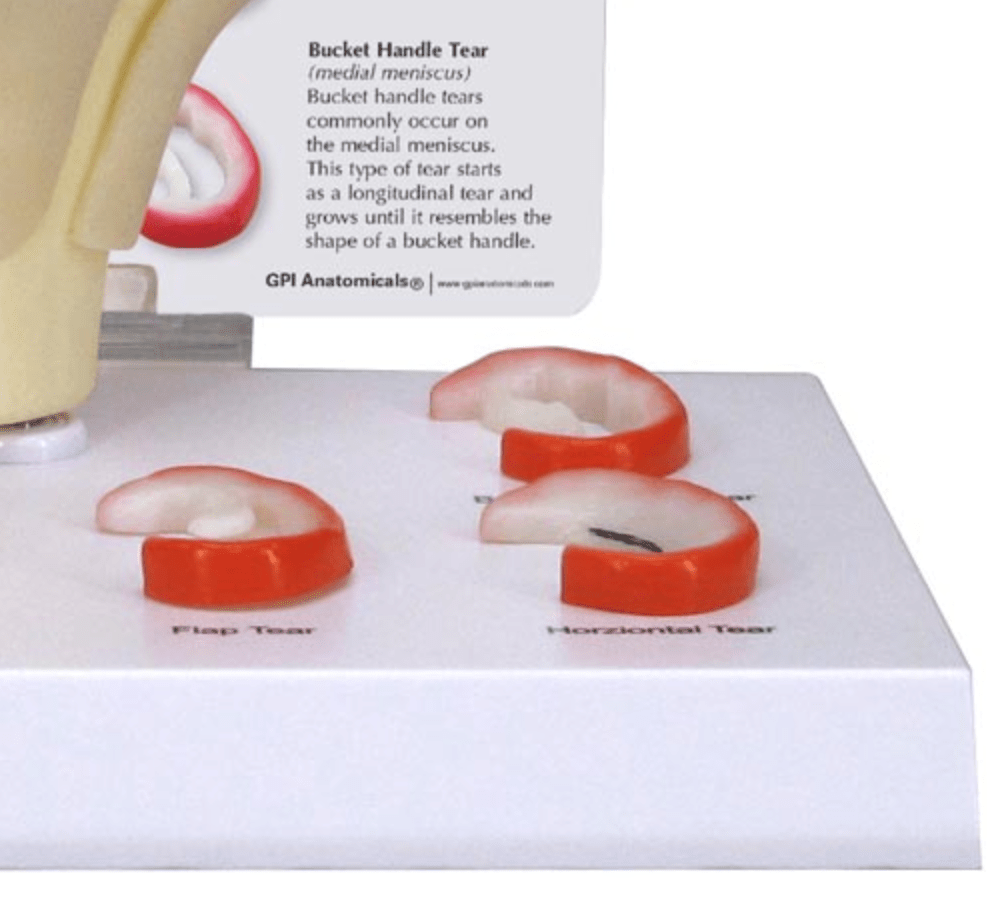

Salg af anatomiske modeller er det bærende element i eAnatomi, selvom vi også bruger mange ressourcer på at udvikle vores egne anatomiske materialer som fx plakater. Anatomiske modeller anvendes til forskellige formål og kan både vise afgrænset væv, organer samt organsystemer. Søger du en simpel model af knoglevæv eller måske en avanceret torso-model baseret på MRI teknologi, kan du finde det hele på eanatomi.com.